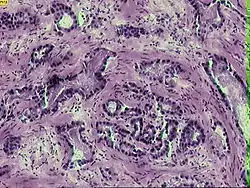

Рак проста́ти (лат. Prostatic adenocarcinoma) — злоякісне новоутворення, що виникає з епітелію альвеолярно-клітинних залоз.

Гістопатологічна класифікація

За гістологічним складом[8] рак простати поділяється на такі форми:

- Недиференційовані

- Поліморфноклітинний рак (велика кількість різних за формою та розміром клітин, що діляться)

- Малодиференційовані

- Анапластична аденокарцинома (зміна внутрішньоклітинних структур, характерні форма й розміри клітин)

- Солідний рак (клітини розміщуються пластами або тяжами, розділеними прошарками з'єднувальної тканини)

- Скіррозний рак (пухлина стає твердою, фіброзною за рахунок переважання строми зі з'єднувальної тканини над пухлинними клітинами)

- Диференційовані

- Аденокарцинома (якщо рак виник із залозистого епітелію)

- Плоскоклітинний (якщо рак виник із плоского епітелію)

- Тубулярний (виникнення з вузьких каналів, застелених епітелієм, у просвіті яких може перебувати секрет)

- Кубічний тубулярний рак

- Призматичний тубулярний рак

- Альвеолярний (виникає з кінцевих відділів гілок залоз)